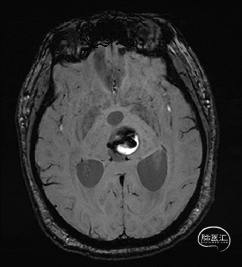

术前MRI检查

术前MRI检查提示左侧丘脑中脑海绵状血管瘤并卒中,梗阻性脑积水;

诊断:1.左侧丘脑中脑海绵状血管瘤并卒中,2.梗阻性脑积水;

年轻患者,较短时间内发生左侧丘脑二次出血,出现右侧面部及上肢麻木,复视,第二次出血后并发梗阻性脑积水,出现头痛。结合病史、神经系统体征、头颅CT及MRI检查,诊断左侧丘脑及中脑CM并卒中、脑积水明确,并导致了神经功能障碍,具备手术指征。

本例患者磁共振检查清晰显示病变位于左侧丘脑中脑区域,且位于丘脑内下方向中脑顶盖延续,病变的上部、前部、外侧部都有重要的神经组织,因此,手术从上方、前方、外侧方向切除病变均难以实施;